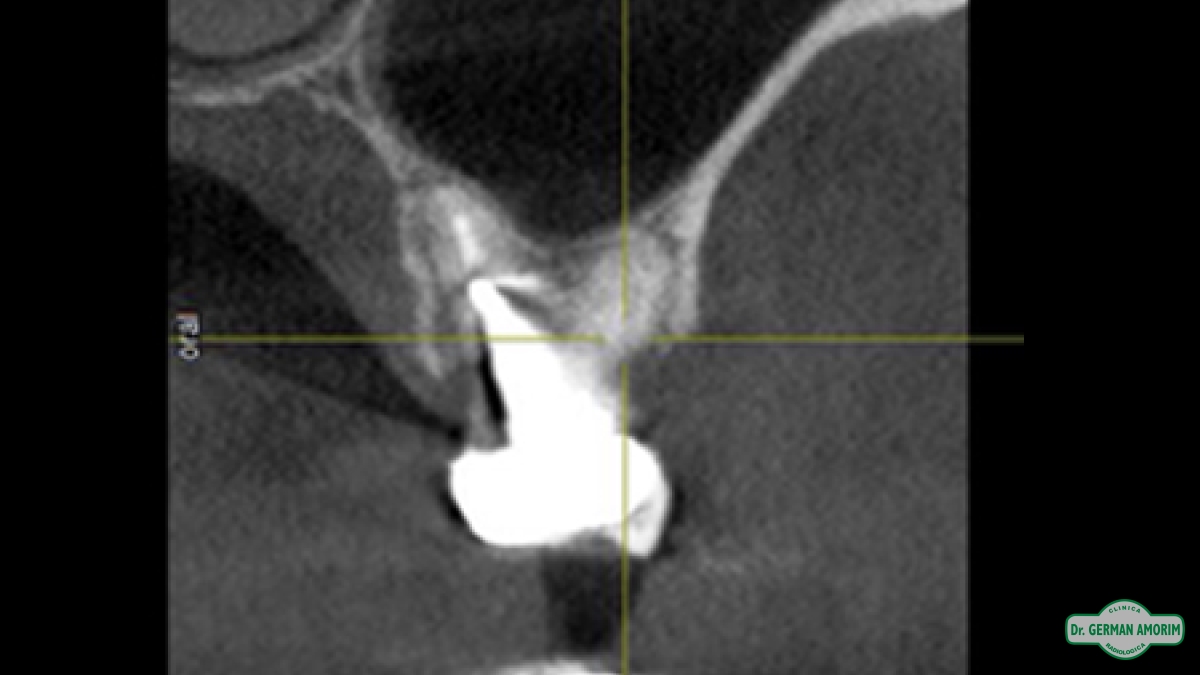

Actualmente y con todos los conocimientos científicos que existen sobre las técnicas implantológicas se recomienda tener siempre una imagen 3D, también en los casos que sea un solo implante. Porque se debe conocer con precisión el espesor de la tabla vestibular para determinar el pronóstico a largo plazo del implante y la única manera de hacerlo es con una tomografía.

El odontólogo utilizando el software específico Galileos puede observar esta imagen en los tres ejes de un espacio tridimensional y trabajar sobre ella para, entre otras cosas, planificar la colocación de los implantes dentales, lesiones ocultas por superposición en las RX convencionales, etc.

• Evaluar si hay hueso suficiente

• Mediciones para ancho y largo del implante

• Determinación de la densidad ósea ya que el sistema permite hacer una densitometría localizada